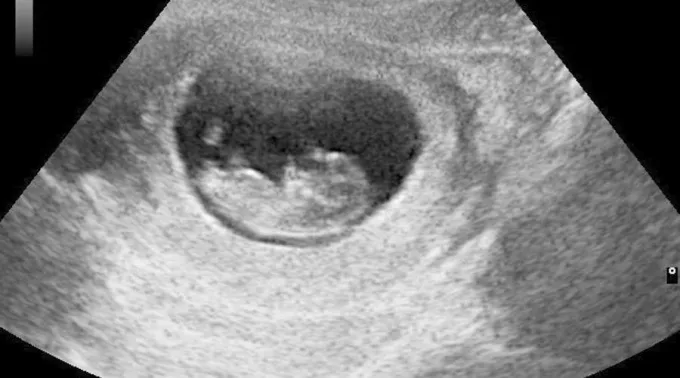

A Lei de "Justiça e Igualdade para Crianças Vivas" LIFE (Vida, na sua sigla em inglês) permite o aborto apenas até a 6ª semana de gestação. Atualmente, o aborto é legal na Geórgia até a 20ª semana.